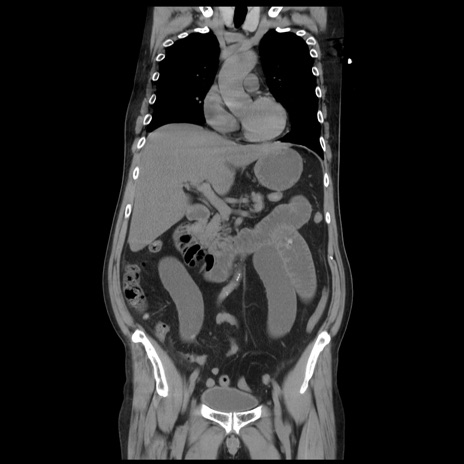

矢状断像